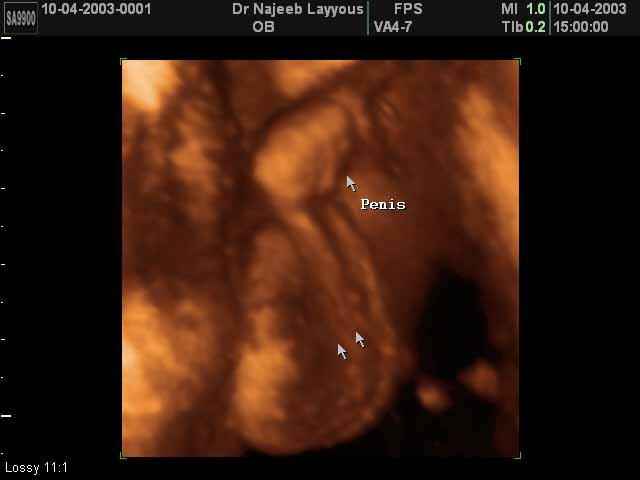

- Fetal Parts Ultrasound Scan Photos